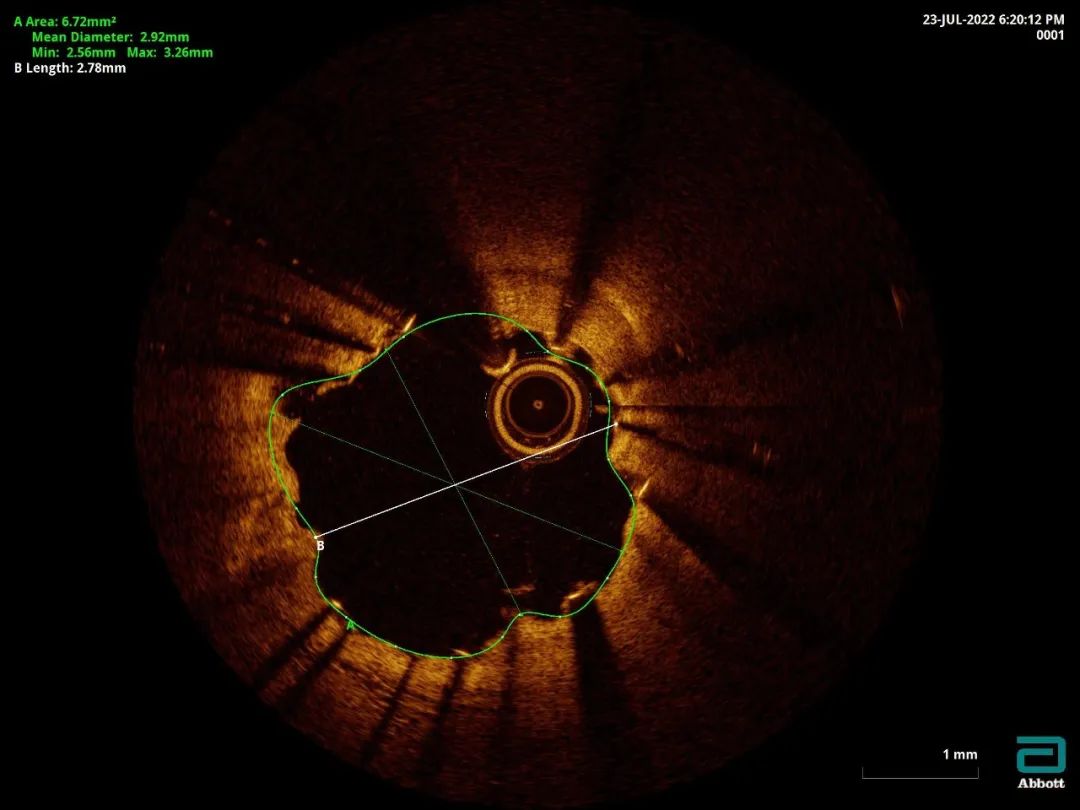

遂使用3.5-12mm Shockwave冲击波球囊4atm共5个周期处理后支架膨胀良好。进一步3.5mm/4.0mm低顺应性球囊后扩修饰。

OCT最终结果显示支架膨胀良好

最后复查OCT示支架贴壁、膨胀良好,支架下钙化断裂。